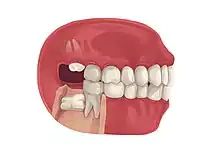

Impacted third molar

3D CT of an impacted wisdom tooth adjacent the inferior alveolar nerve prior to removal of wisdom tooth